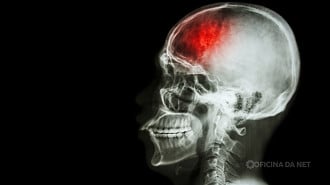

A inteligência artificial e os sensores inteligentes devem revolucionar a medicina já em 2026 e o Brasil pode ter papel importante nisso. Segundo a pesquisadora Suélia Fleury Rosa, membro sênior do IEEE e professora da Universidade de Brasília, o avanço dos chamados gêmeos digitais, que são versões virtuais de órgãos ou sistemas do corpo humano, vai permitir prever e até evitar doenças graves como AVC e cegueira.

Esses gêmeos digitais são modelos computadorizados alimentados com dados de sensores que monitoram o corpo em tempo real. Quando cruzadas com algoritmos de IA, essas informações ajudam médicos e engenheiros biomédicos a identificar riscos antes mesmo que os sintomas apareçam.

De forma prática, essas tecnologias devem ajudar a detectar precocemente riscos de AVC, evitar perda de visão com base em dados coletados em escolas e reduzir lesões em atletas com o uso de ressonâncias magnéticas mais inteligentes. Além da saúde, a IA também vai otimizar processos industriais e acelerar a certificação de novas tecnologias em órgãos como o Inmetro, reduzindo custos e riscos.